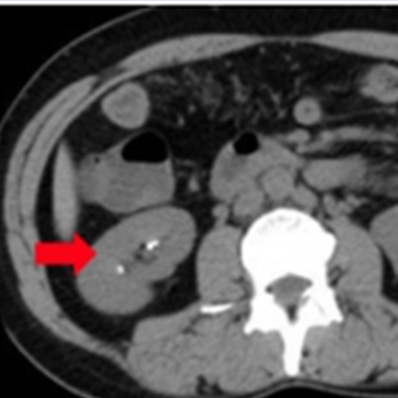

両腎結石症